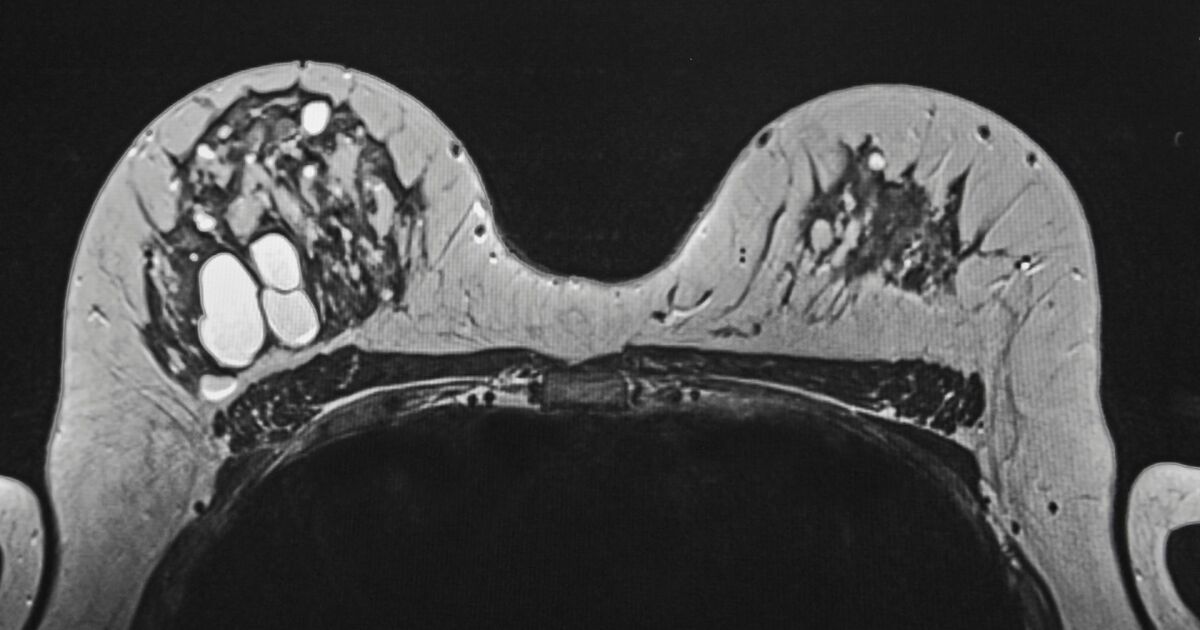

Плътността на гърдите се отнася до съотношението между жлезистата и съединителната тъкан спрямо мастната тъкан, което се вижда на мамография. Казано по-просто, плътните гърди имат повече жлезиста и фиброзна тъкан и по-малко мазнина.

Тази характеристика създава сериозен проблем по време на стандартния скрининг, тъй като и плътната тъкан, и туморите изглеждат бели на мамограмата. Този маскиращ ефект може да доведе до пропускане на аномалии, което прави плътността на гърдите рисков фактор не само за развитие на рак, но и за забавяне на неговото откриване до по-напреднал стадий.

За да се компенсира това ограничение, допълнителни методи за скрининг като ядрено-магнитен резонанс (ЯМР) могат да помогнат за откриване на ракови образувания, които мамографията би пропуснала при жени с плътната гръдна тъкан. Пилотни проучвания показват, че по този начин се откриват допълнителни случаи на рак.